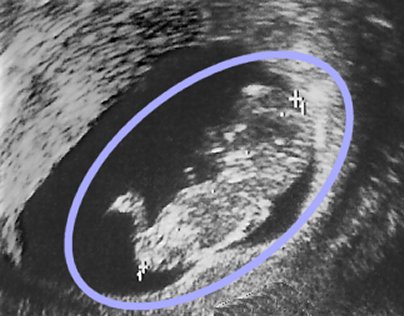

A terhesség harmadik hónapjában felvett sonogram egy hímnemű fötuszt mutat (fej, test és lábak tisztán felismerhetők a kék ovális körön belül).